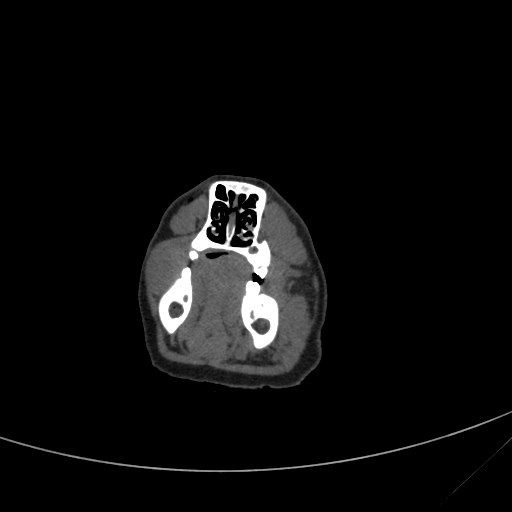

The rendered slice. Coudn't tell you what part of the anatomy this is!